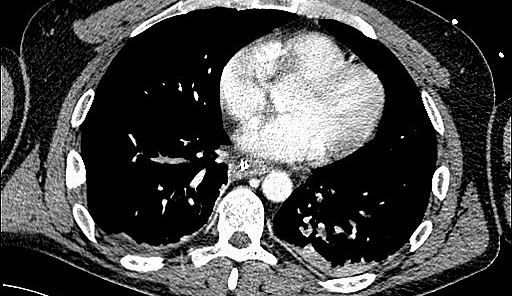

Umgekehrt kann es jedoch auch im Rahmen einer akuten Nierenschädigung zu einer zunehmenden Schädigung und Funktionseinschränkung der Lunge kommen. „Dies kann zum Beispiel durch einen Flüssigkeitsüberschuss bedingt sein, wenn die Niere aufgrund ihrer Schädigung eine adäquate Flüssigkeitsausscheidung nicht mehr aufrechterhalten kann. In weiterer Folge kann dies ein Lungenödem zur Folge haben“, erklärt Intensivmediziner Joannidis. Durch entsprechende vorsichtige Flüssigkeitsbilanzierung beziehungsweise Unterstützung der Flüssigkeitsausscheidung mit harntreibenden Medikamenten oder Nierenersatztherapie (Dialyse) könne dieser Komplikation, so ein Ergebnis der Untersuchung, vorgebeugt werden. Des Weiteren konnten verschiedene Effekte von extrakorporalen Systemen, wie eine „künstliche Niere oder Lunge“, auf die Organfunktionen aufgezeigt werden. „Insbesondere die Kombination von extrakorporalen Systemen stellt Ärztinnen und Ärzte vor neue Herausforderungen und Fragestellungen, wodurch auf diesem Gebiet sich einige neue Forschungsfragen ergeben haben“, sagt Michael Joannidis. So konnten insgesamt mit Ergebnissen der Untersuchung sowohl Empfehlungen für die direkte Patient:innenenversorgung als auch weitere Fragestellungen für zukünftige Forschungsschwerpunkte formuliert werden.